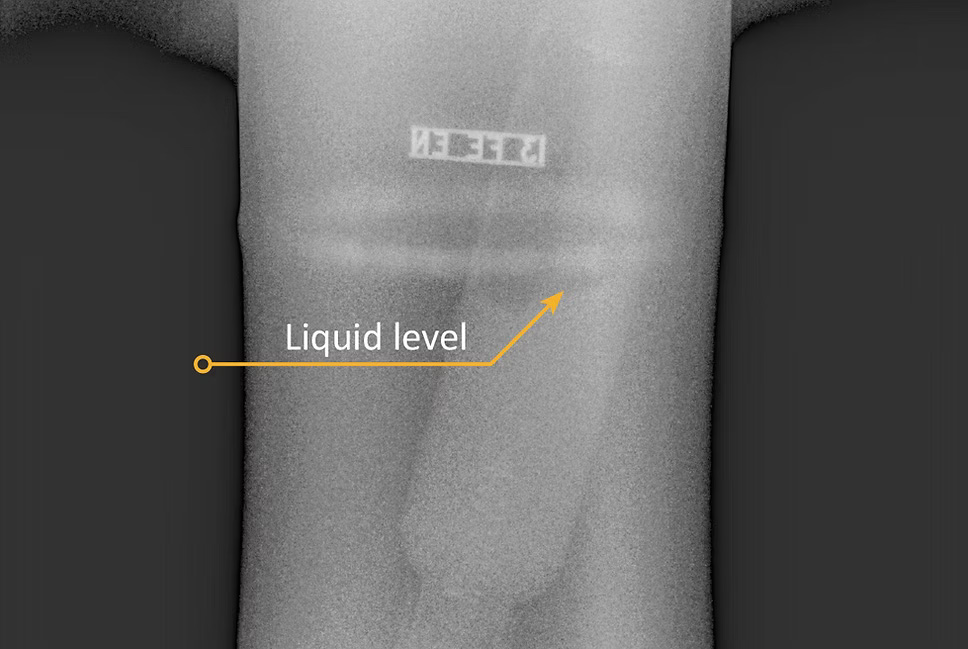

Maksimal bildekvalitet

Gir skarpere, renere og mer presise bilder som gjør beslutninger enklere og mer pålitelige.